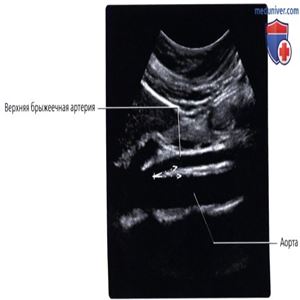

УЗИ, сагиттальный срез: у этой же пациентки определяется сужение пространства между аортой и ВБА. Ножки циркуля обозначают аортобрыжеечный угол, значительно суженный до 11,9 градусов, что является признаком синдрома ВБА, в особенности с учетом анамнестических данных.